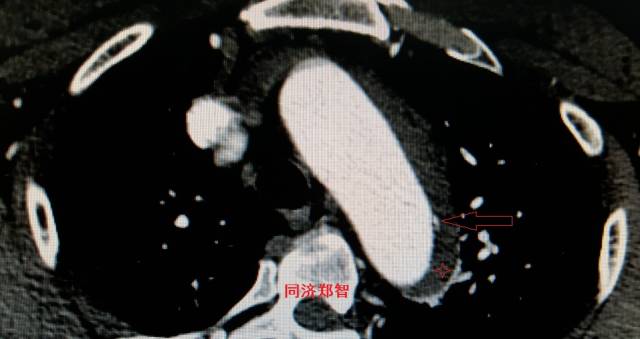

病例十

腹主动脉平扫CT提示正常外周一圈的钙化影中有内移的钙化影(红色箭头所示),CTA 证实为腹主动脉夹层。